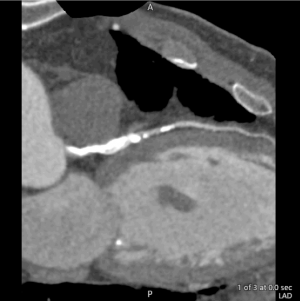

70-jähriger Patient mit Pavk, KHK 3-GE und 5-fach DES (3xRCA, 1xRIVA, 1xRCX)

RIVA CT-Angiografie ohne Subtraktion:

Mit Subtraktion Kalk/Stent:

Um Blutgefäße mit Stents oder sehr viel Kalk dreidimensional im CT zu untersuchen, wird eine besondere Form der Angiographie mit Kontrastmittel angewandt: die digitale Subtraktionsangiographie (DSA). Ihr Vorteil gegenüber der konventionellen Angiographie besteht darin, dass durch die Subtraktion störende Elemente wie Stents oder starke Verkalkungen aus dem CT-Bild herausgerechnet werden. Hierzu wird zunächst ein CT-Volumendatensatz des Herzens ohne Kontrastmittel angefertigt.

Nach der Injektion von Kontrastmittel erfolgt ein weiterer CT-Scan des Herzens. Der Computer generiert auf Basis beider Aufnahmen danach ein DSA-Bild. Der Effekt: Beim DSA-Bild sind nur die kontrastmittelgefüllten Blutgefäße zu sehen, alle anderen Strukturen sind weitestgehend ausgeblendet. Somit können wir Verengungen auch unter schwierigsten Bedingungen wie im Herzkatheter sehr gut erkennen, exakt ausgemessen und adäquat reagieren.